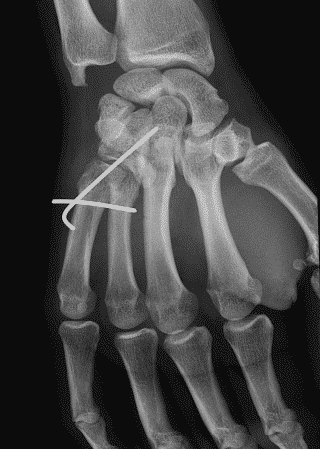

Lorsque la fracture de base touche l'articulation, il y a une tendance à la subluxation dorsale. On réalise alors un brochage prenant appui sur les os sains adjacents (illustration ci-dessus). Cela permet à la fois de fixer la fracture et réduire la subluxation.

L'immobilisation post-opératoire est en revanche différente. Habituellement on immobilise le poignet tout en laissant les doigts libres.